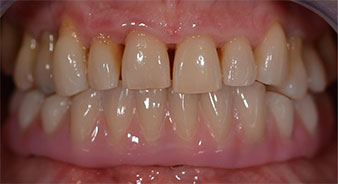

The 64-year-old patient presented with residual dentition of teeth 38, 33 and 43 and a clasp denture in the mandible (Fig. 1 and 2).

Following the time required for the osseointegration, the final impression of the implants could be performed and the final denture produced accordingly (Fig. 19 and 20). At this point, the dentist and patient were able to decide together whether to use a ceramic or acrylic veneer and a zirconium or metal framework. In this case, Dr. Pascu’s team decided on an acrylic veneer based on the unclear prognosis for the maxillary dentition and the fact that tooth 24 is elongated. This type of veneer is generally considerably easier to adapt and can thus be subsequently altered to reflect the new situation in the maxilla.